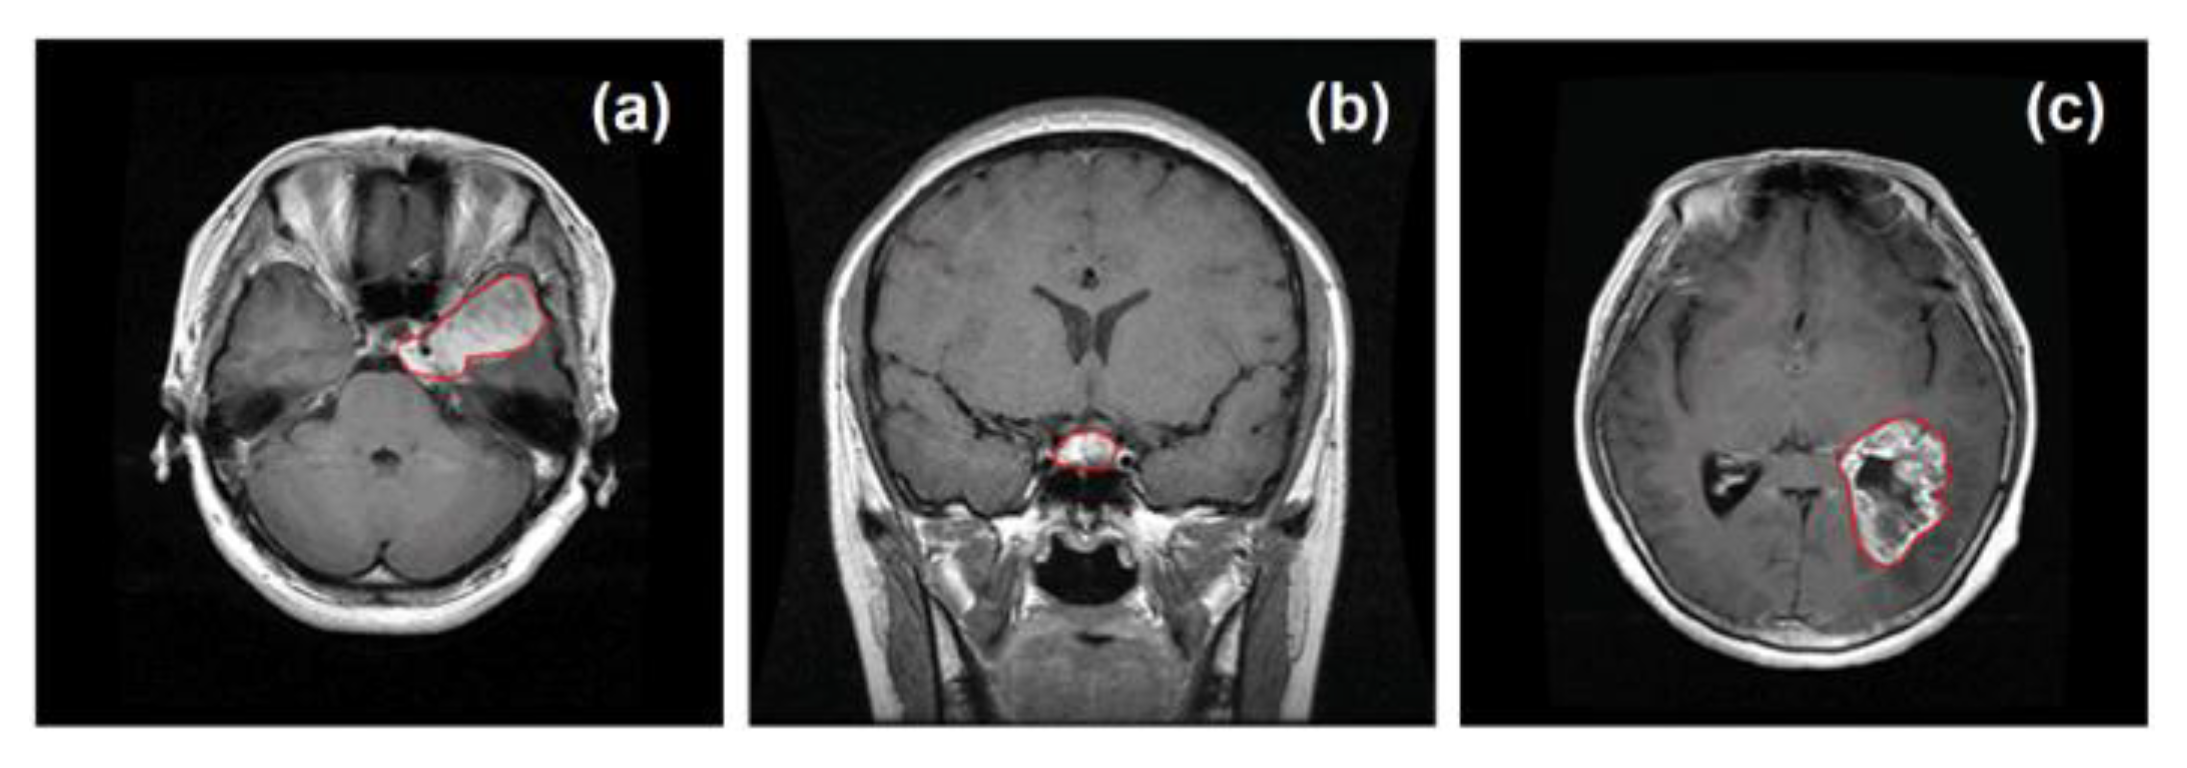

2. Literature Review

3.4. Brain Tumor Diagnosis Using MRI Data